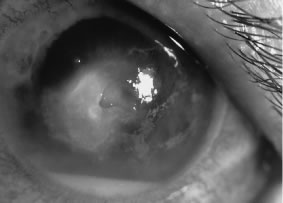

Candida infection typically produces epithelial ulceration, focal necrotizing stromal inflammation, moderate cellular infiltrate and edema in the adjacent stroma, and mild or moderate iritis in the early stages, indistinguishable from bacterial keratitis (Figs. 15, 16, and 17). Fungal elements cannot be detected by biomicroscopy. If untreated, the keratitis evolves to produce dense suppuration and necrosis of the deep stroma. Although multifocal suppuration may develop in polymicrobial keratitis, there is no distinctive sign of mixed Candida and bacterial infection (Fig. 18).

Fig. 15. C. albicans keratitis in an eye following chronic use of corticosteroid drops for herpes simplex keratitis. Note the central suppuration and perforation, endothelial plaques, and hypopyon.